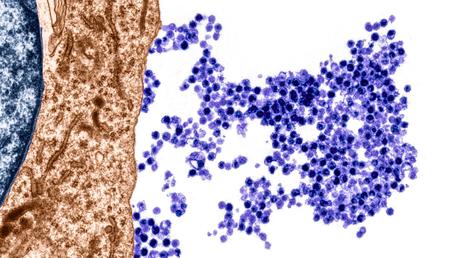

Un microbio sorprendentemente masivo: Se supone que los microbios son microscópicos, pero un nuevo microorganismo llamado Thiomargarita magnifica, puede ser 5000 veces más grande que muchas células bacterianas. Las células únicas, parecidas a hilos, se vieron por primera vez en la superficie de las hojas moribundas en un manglar en las Antillas francesas.

Vacunas contra el VRS o virus respiratorio sincitial: Los ensayos clínicos a gran escala de dos vacunas contra el virus respiratorio sincitial finalmente han demostrado que pueden proteger de manera segura a los dos grupos más afectados por esta infección común: bebés –incluso recién nacidos mediante la vacunación de sus madres- y ancianos. Hablamos de un virus que está muy de moda últimamente.

Se ha identificado un virus como causante de la esclerosis múltiple: Basándose en una gran cantidad de registros médicos militares, los investigadores demostraron en 2022 que un virus de la familia de los herpes –El Epstein-Barr– es un actor esencial en la esclerosis múltiple (EM), una enfermedad en la que el sistema inmunitario ataca las células que protegen a las neuronas.